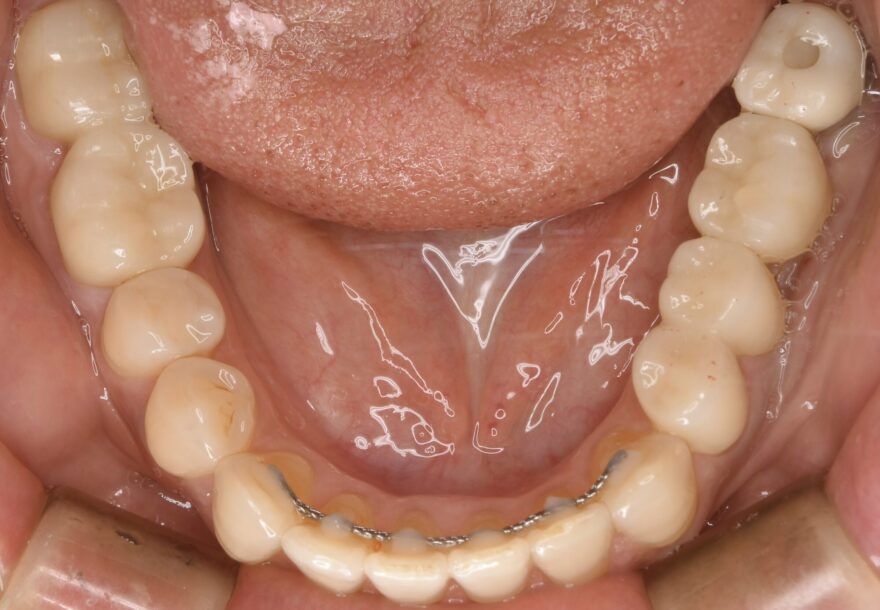

治療後の口腔内写真

下顎の前歯にも、後戻り防止のためのワイヤーを装着しています。